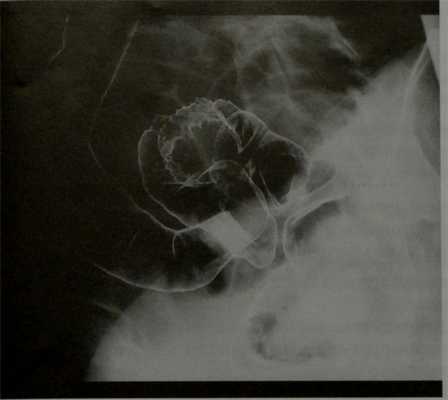

Поражение кишечника наблюдается у 4-37% женщин с данным заболеванием. Первым методом исследования при подозрении на вовлечение кишечника является трансвагинальное УЗИ. Кроме того, для определения глубины инвазии стенки кишки, протяженности поражения и расстояния до ануса может использоваться МРТ.

Покажет ли МРТ эндометриоз? На Т2 взвешенных сагиттальных МР-томограммах визуализируются два патологических веерообразных участка, дающих гипоинтенсивный сигнал (красные стрелки). Эти изменения типичны для эндометриоза с инфильтрацией стенки кишечника. Также определяется подслизистый отек, характеризующийся гиперинтенсивным сигналом со стороны отделов стенки кишки, расположенных ближе к просвету

Эндометриоз на МРТ малого таза. В случае циркулярного поражения эндометриоидная инфильтрация может приводить к сужению просвета кишечника. У пациенток при этом возможно изменение формы каловых масс (они становятся узкими в виде «карандаша») либо запоры. На Т2 взвешенных сагиттальных МР-томограммах определяется стеноз прямой кишки на ограниченном участке вследствие циркулярной инфильтрации